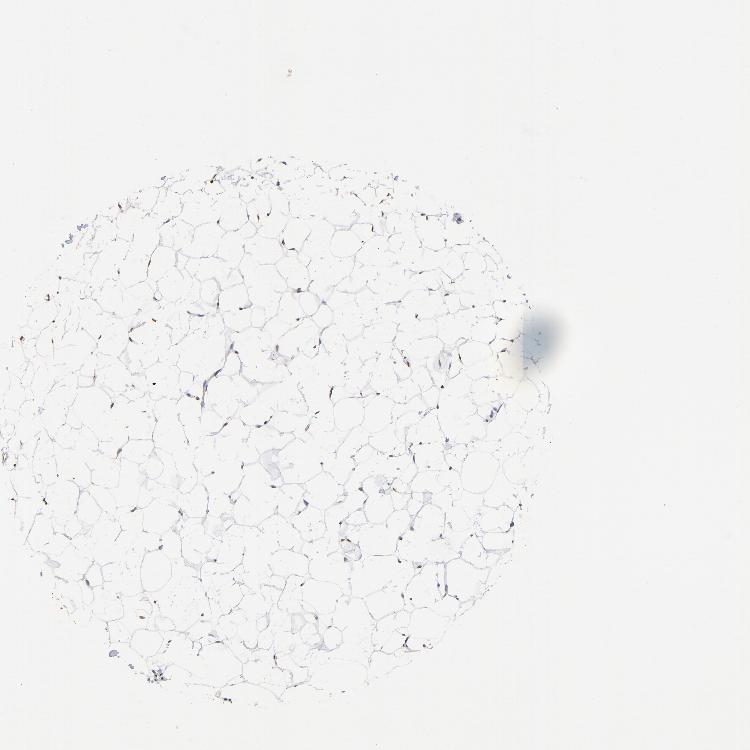

SOFT TISSUE 2 - Antibody stainingi

Antibody staining in the annotated cell types in the current human tissue is reported as not detected, low, medium, or high, based on conventional immunohistochemistry profiling in selected tissues. This score is based on the combination of the staining intensity and fraction of stained cells.

Each image is clickable and will lead to virtual microscopy that enables deeper exploration of all samples and also displays staining intensity scores, fraction scores and subcellular localization as well as patient and tissue information for each sample.

Antibody HPA003359

Chondrocytes Low

Fibroblasts Low